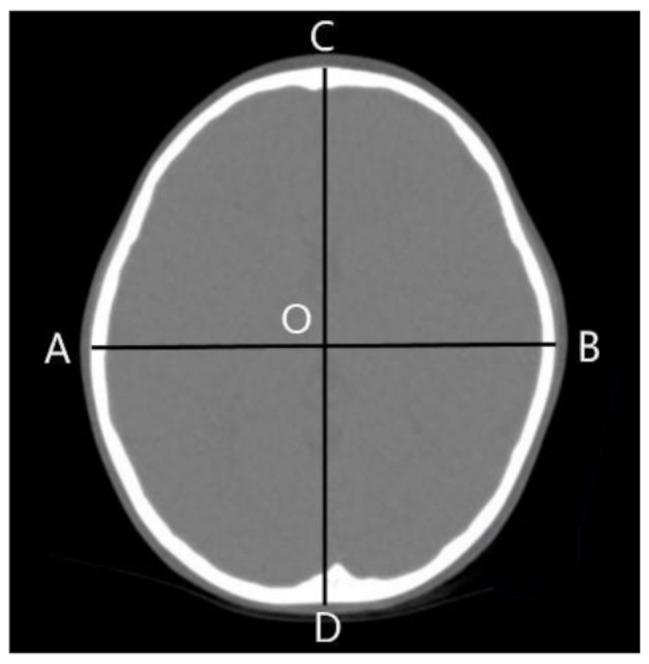

We retrospectively analyzed Chinese Han children who visited our hospitals between June 2015 and June 2020 because of headache or suspected head injuries. 456 children (257 males, 199 females; aged 0-15 years) were enrolled and divided into 7 groups by age. The values of CI and H-PMW were measured using thin-slice brain computed tomography images.

The overall mean CI was 86.6 ± 5.2. The mean CI for males was 87.0 ± 5.1, and that for females was 86.0 ± 5.2. The overall mean H-PMW was 53.7 ± 2.4. The mean H-PMW for males was 53.8 ± 2.5, and that for females was 53.5 ± 2.3. The averages CI reached the maximum (89.98) at the age of 4-6 months, then began to decrease, decreased to the minimum (84.31) at the age of 2-3 years, and then gradually increased, and reached 86.17 at the age of 8-15 years. The average H-PMW was the smallest (52.17) at the age of 4-6 months, and reached 54.88 at the age of 8-15 years.

我们回顾性分析了 2015 年 6 月至 2020 年 6 月期间因头痛或疑似头部受伤而到我院就诊的汉族儿童。共纳入 456 名儿童(男 257 名,女 199 名;年龄 0-15 岁),并按年龄分为 7 组。使用薄层脑 CT 图像测量 CI 和 H-PMW 值。

总体平均 CI 为 86.6±5.2。男性的平均 CI 为 87.0±5.1,女性为 86.0±5.2。总体平均 H-PMW 为 53.7±2.4。男性的平均 H-PMW 为 53.8±2.5,女性为 53.5±2.3。CI 平均值在 4-6 个月时达到最大值(89.98),然后开始下降,在 2-3 岁时降至最小值(84.31),然后逐渐增加,在 8-15 岁时达到 86.17。H-PMW 平均值在 4-6 个月时最小(52.17),在 8-15 岁时达到 54.88。